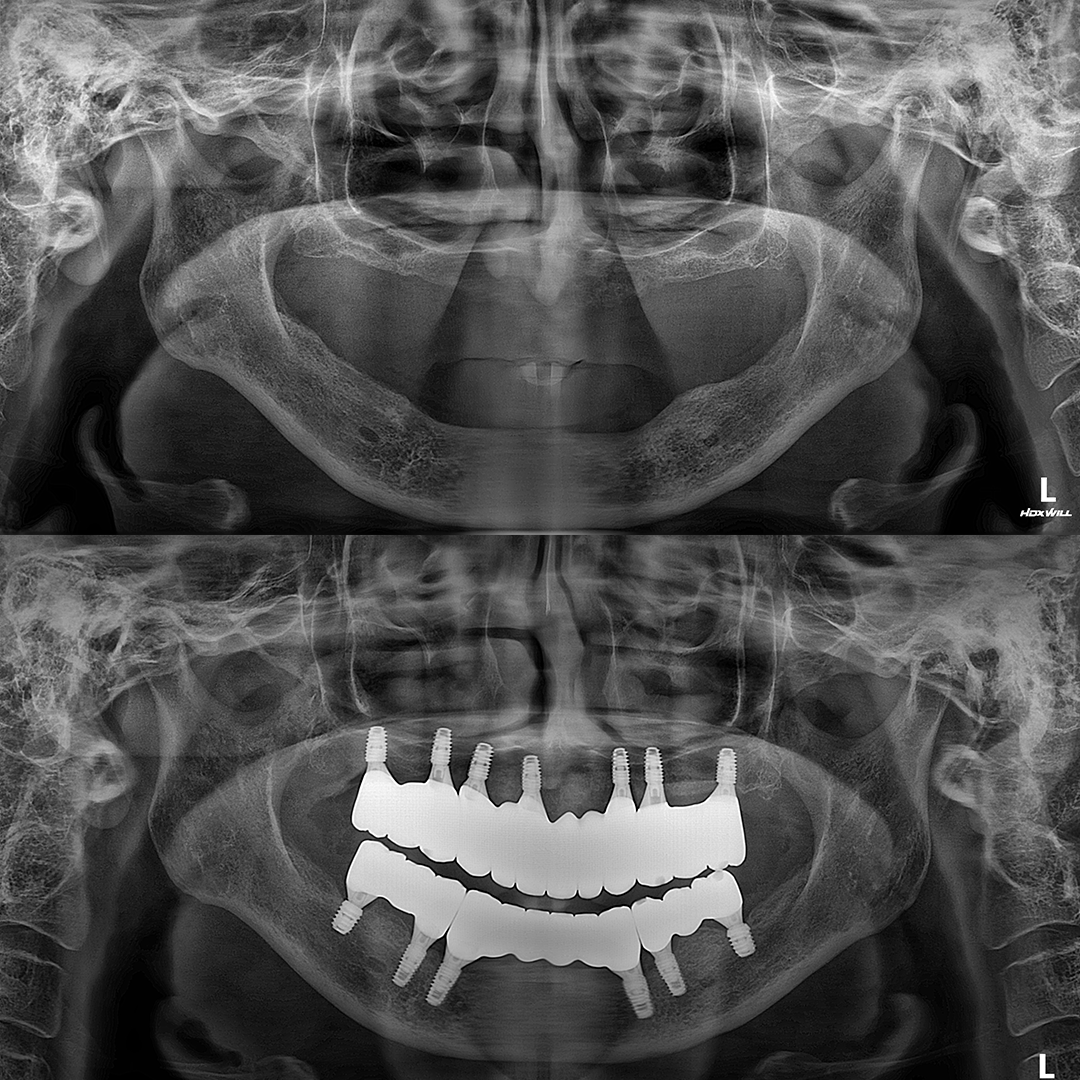

전체 임플란트

상·하악 전체 치아를 대체하는 임플란트로 최소한의 식립을 통해

자연치아와 비슷한 기능을 수행할 수 있도록 합니다.